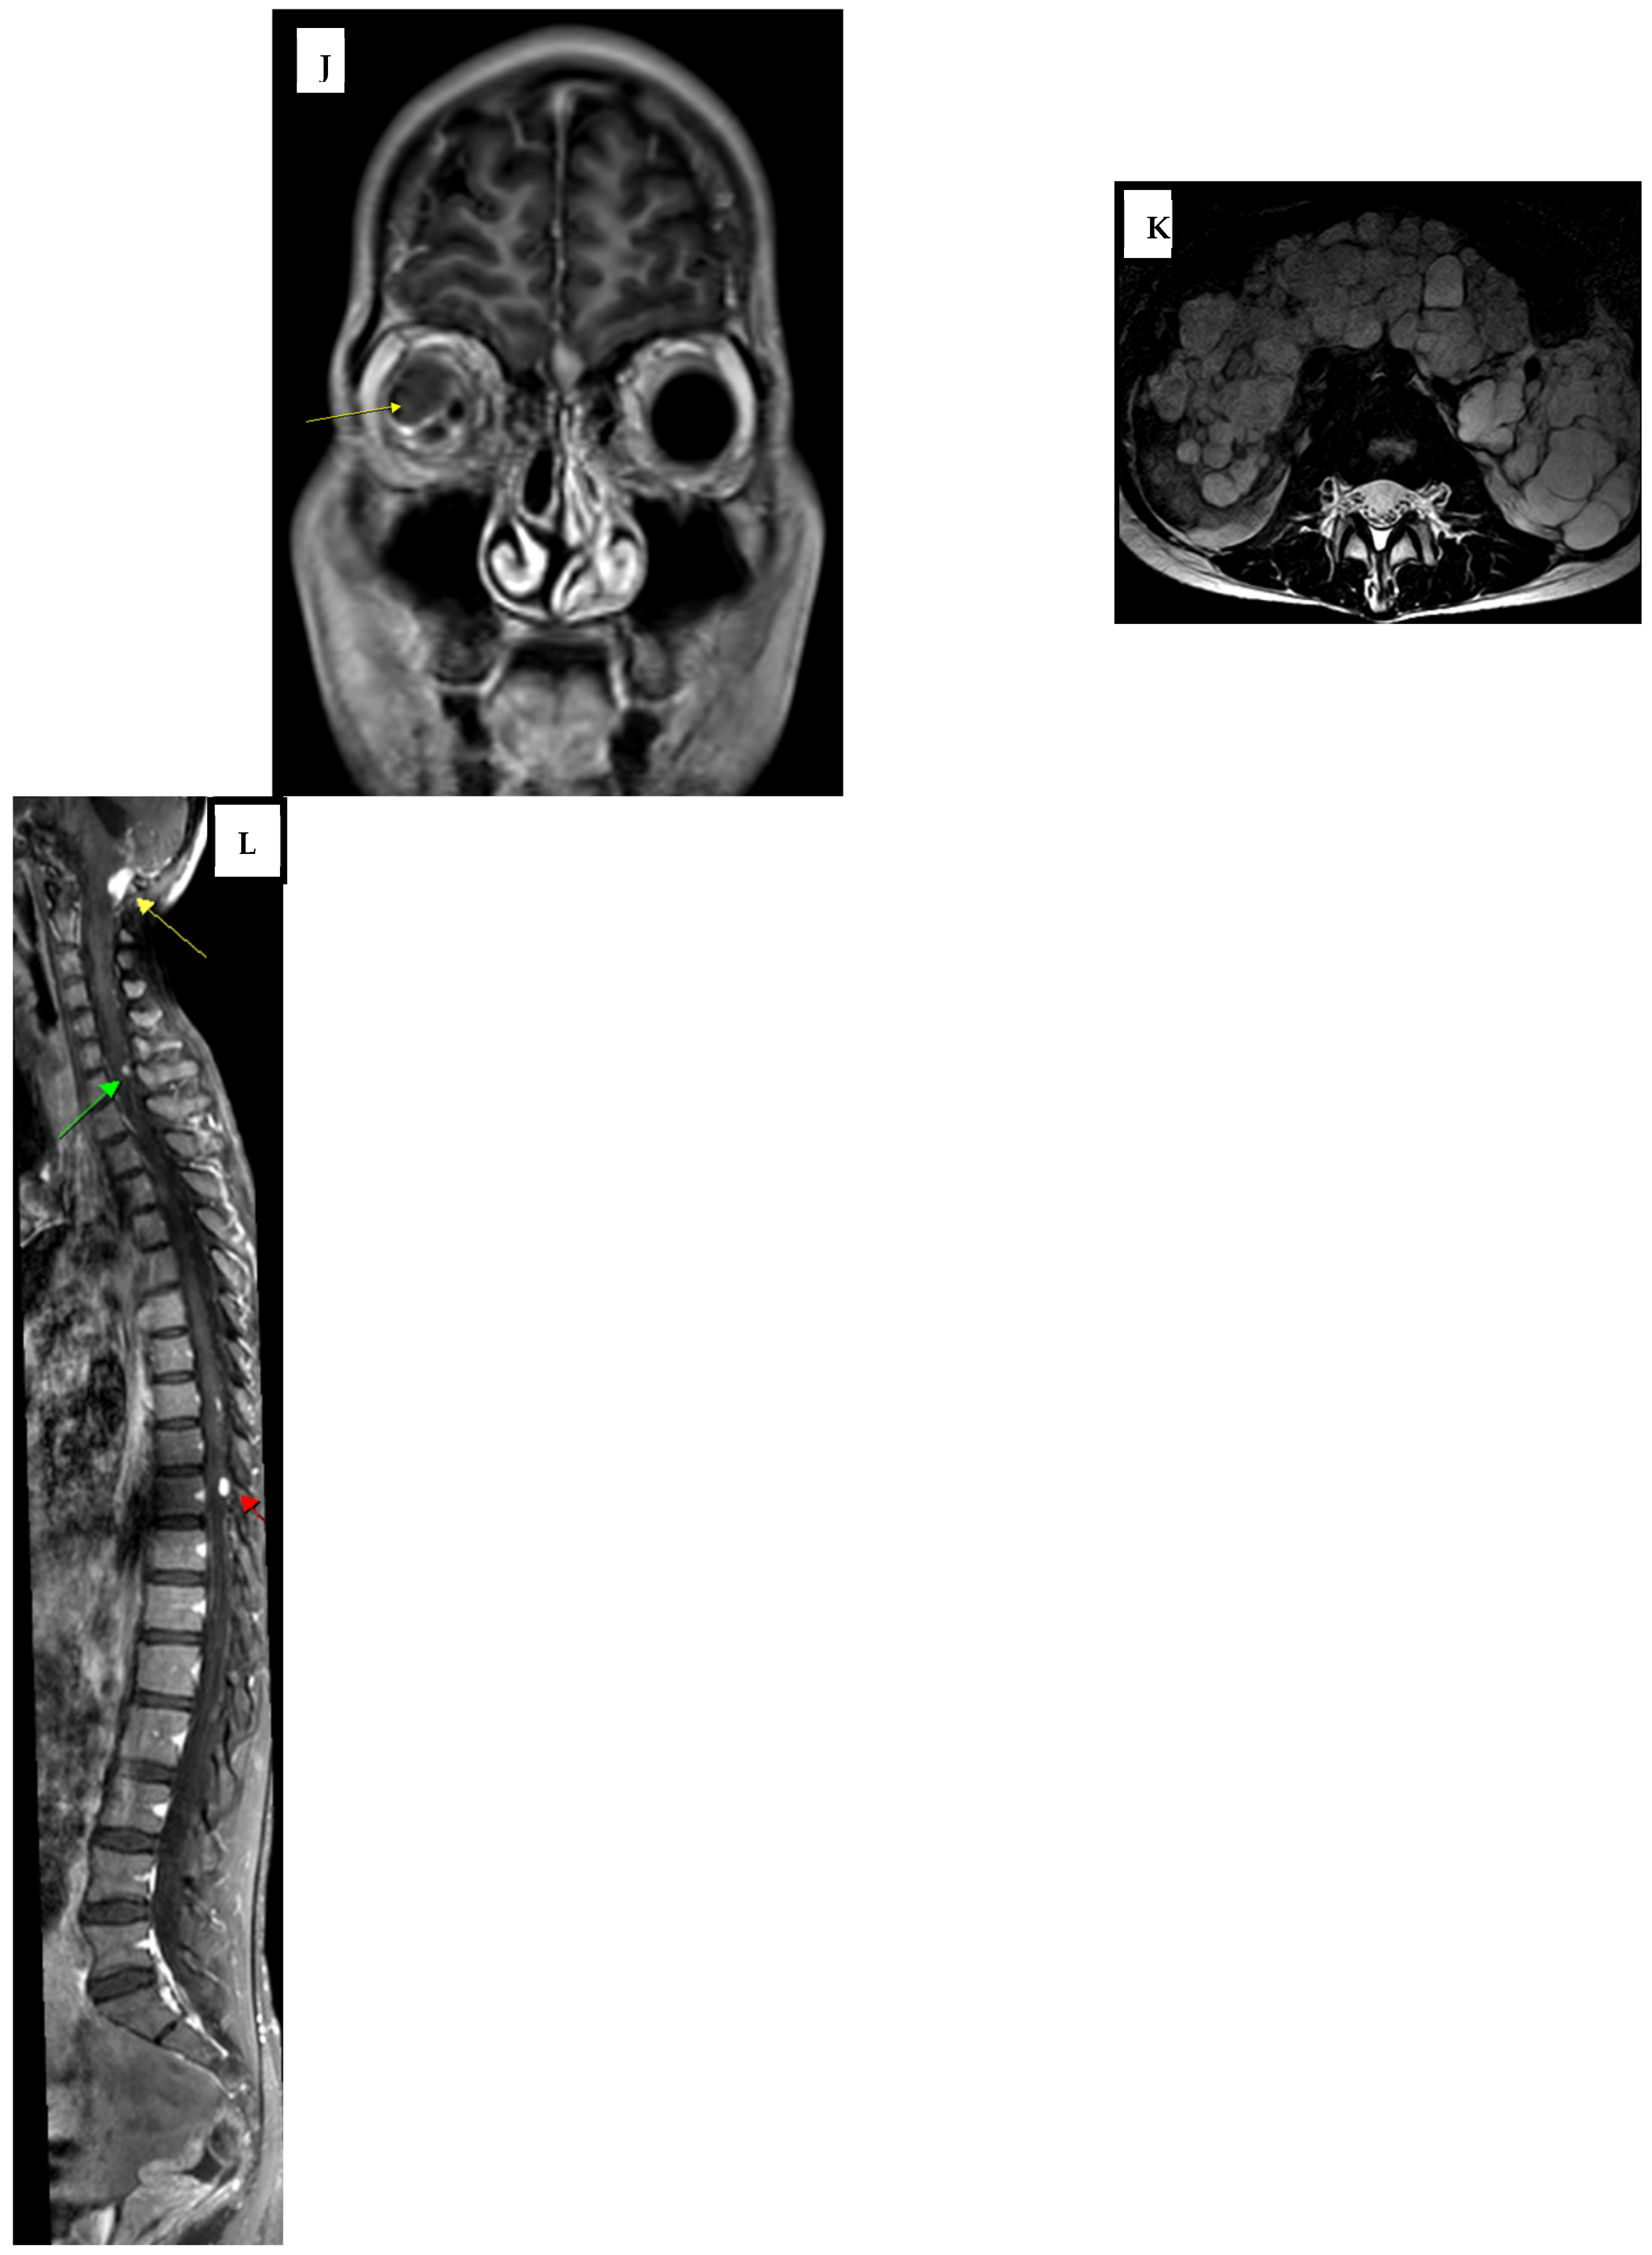

2. Case Report

| Time Point | 4th Ventricular Lesion | Retrobulbar Lesion | Spinal Lesions | Notes |

|---|---|---|---|---|

| Initial (Year 0) | 19 mm | 11 mm | Not checked | Pre-GKS |

| After two GKS sessions (Year 1) | 12 mm | 11 mm | Not checked | Partial regression |

| Lost to follow-up (Year 3) | 12 mm | 11 mm | Detected nodules in C1-C2, C6 and T8 | Progression |

| Post-progression imaging | Stable | Stable | Multiple | Observation phase |

| Final follow-up (Year 9) | Stable | Stable | Stable | Conservative management |